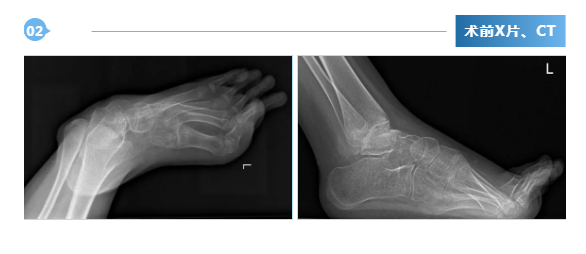

广东医附院创伤骨科成功开展ilizarov技术,治疗脑瘫马蹄足畸形

近日,我院创伤骨科在吴浩俊主任医师的带领下,由陈继铭、刘田丰、陈周韬、潘开翔等组成的足踝医师技术团队,在麻醉手术中心、创伤骨科护理团队的共同努力下,成功为1名脑瘫后马蹄内翻足畸形患者成功实施了 ilizarov环形外固定架矫形手术。患者黎某某,女,12岁,因“双...2024-05